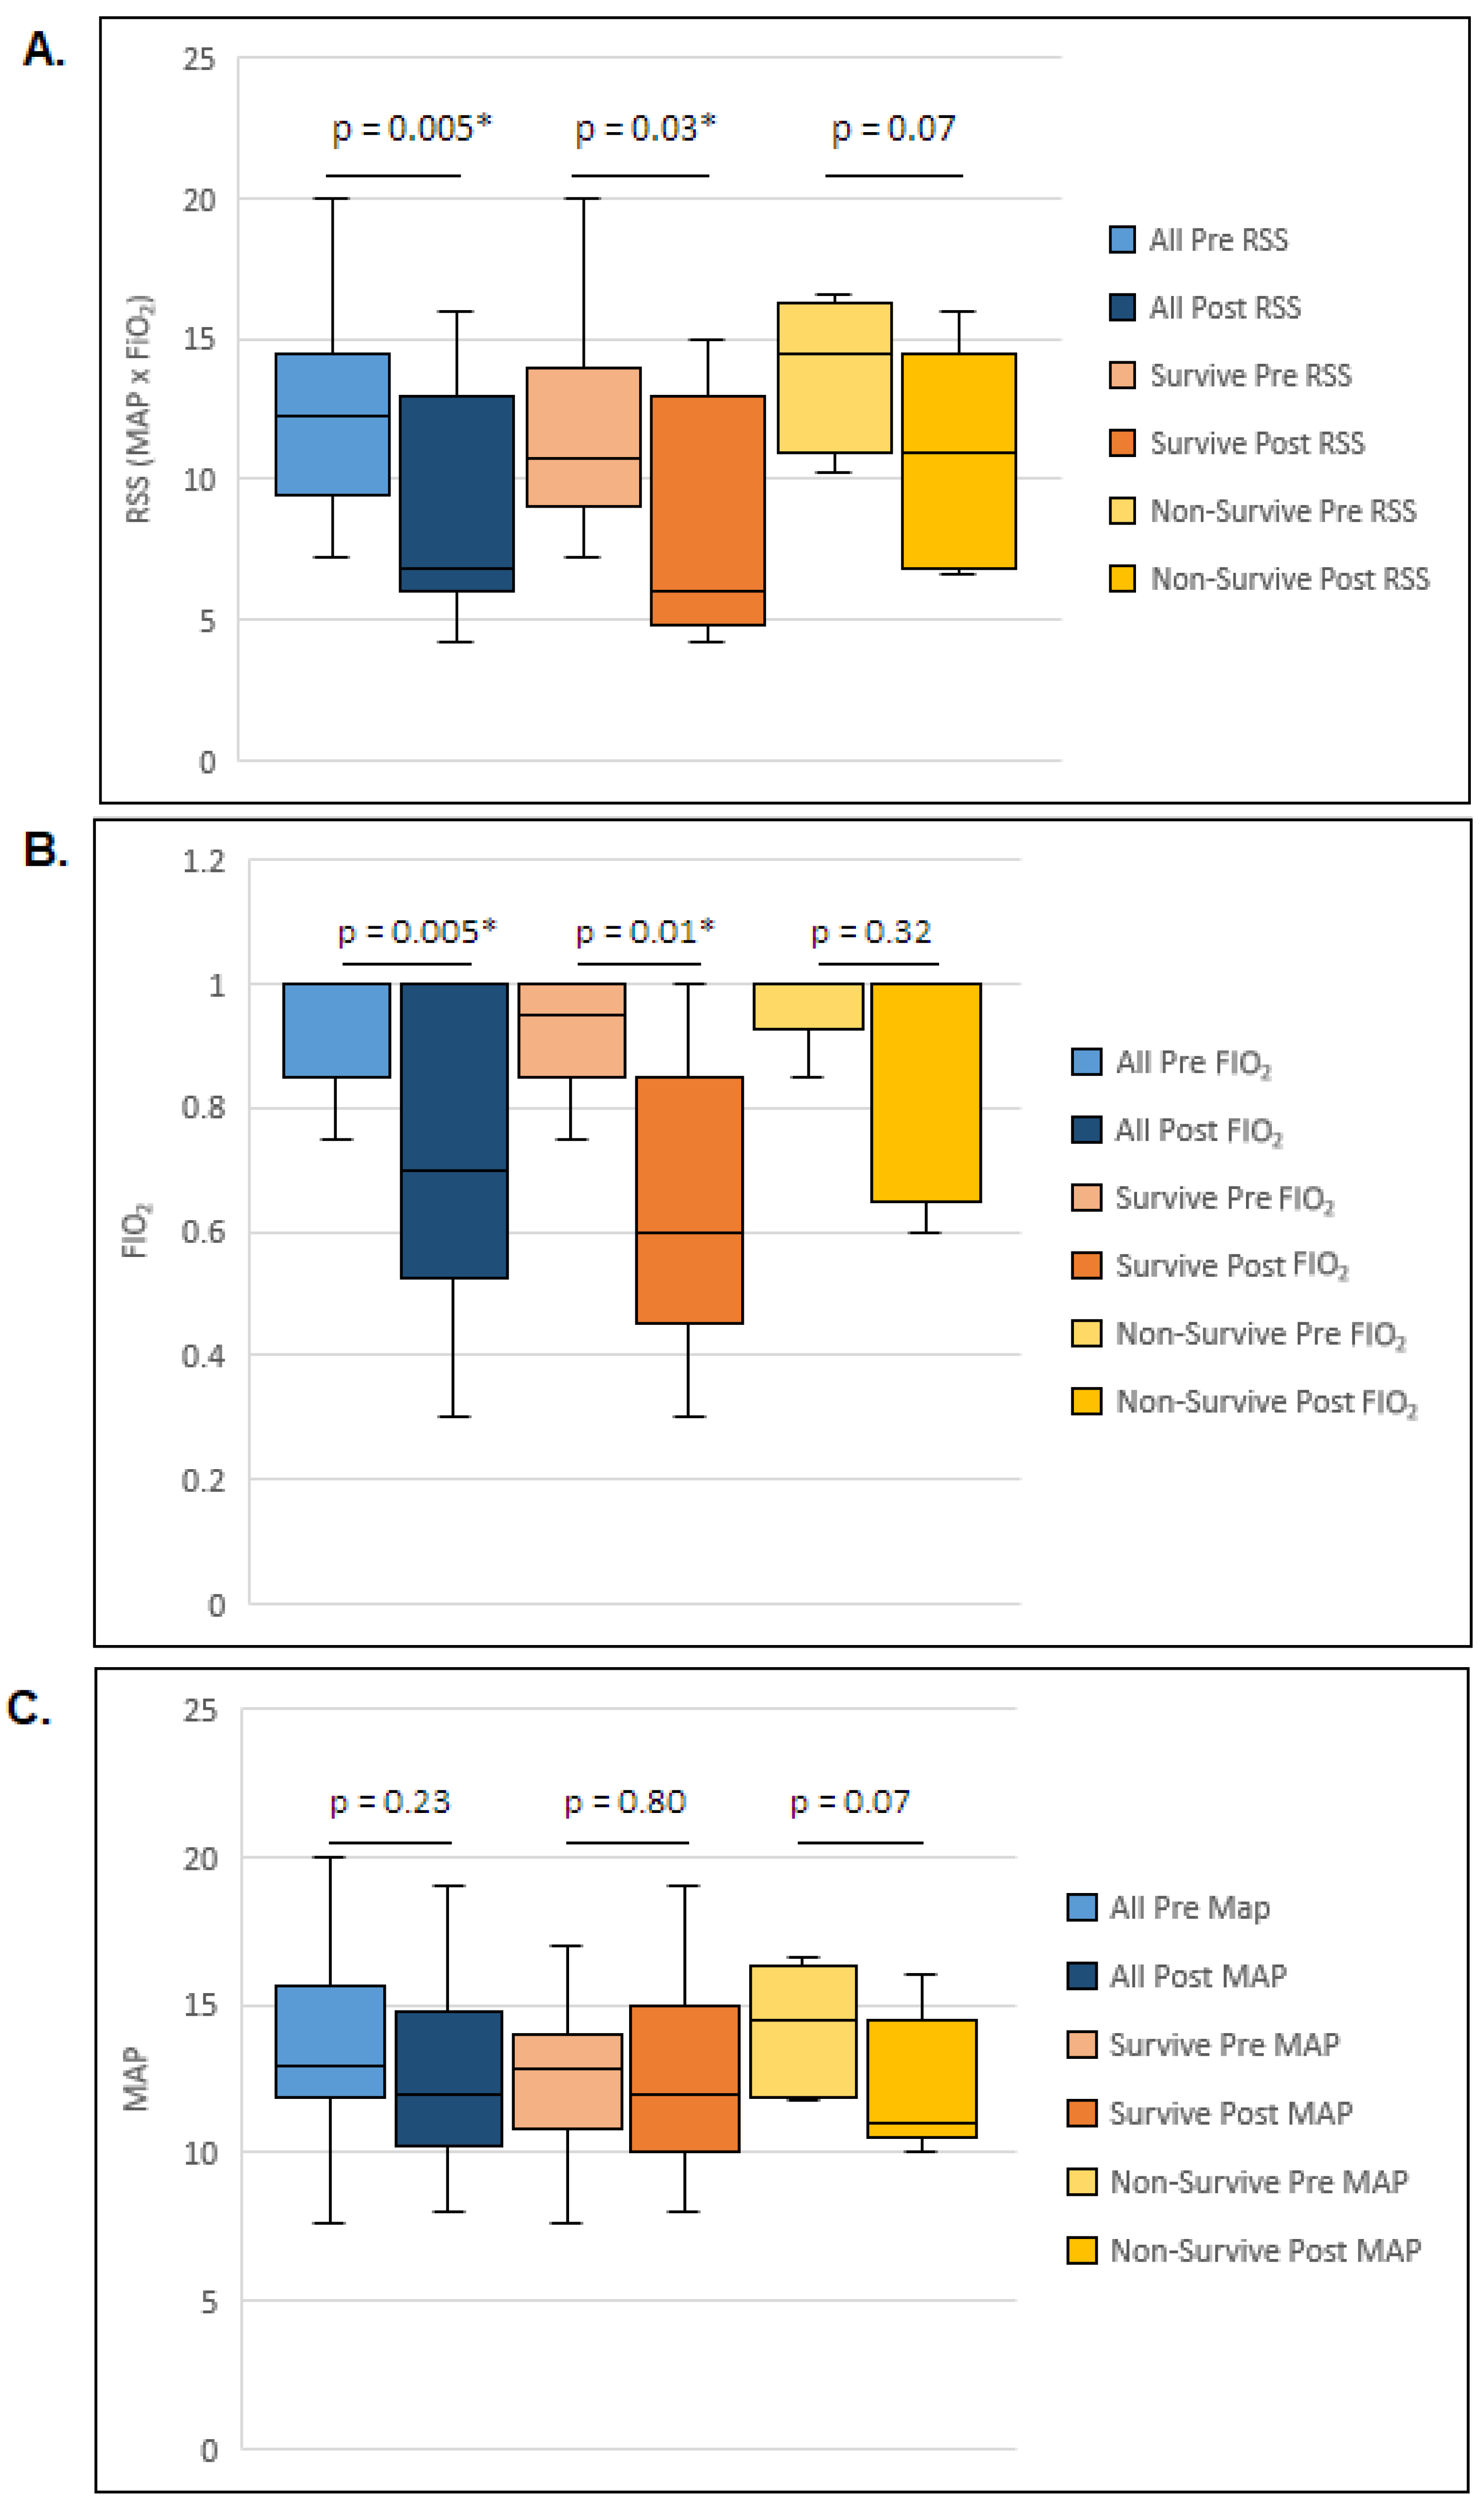

| Pre-HFPV FiO2 (median, IQR) | 1 (0.85, 1) |

| Post-HFPV FiO2 (median, IQR) | 0.7 (0.53, 1) |

| Pre-HFPV MAP (median, IQR) | 13 (12, 16) |

| Post- HFPV MAP (median, IQR) | 12 (10, 15) |

| Pre-HFPV RSS (median, IQR) | 12 (9, 15) |

| Post-HFPV RSS (median, IQR) | 7 (6, 13) |

| RSS Change (median, IQR) | 3 (0.65, 8) |

| Pre-HFPV FiO2 (median, IQR) | 0.95 (0.85, 1) | 1 (1, 1) | 0.31 |

| Post-HFPV FiO2 (median, IQR) | 0.6 (0.4, 0.9) | 1 (0.7, 1) | 0.12 |

| Pre-HFPV MAP (median, IQR) | 13 (10.8, 14) | 15 (11.9, 16.3) | 0.49 |

| Post-HFPV MAP (median, IQR) | 12 (10, 15) | 11 (10.5, 14.5) | 0.89 |

| Pre-HFPV RSS (median, IQR) | 11 (9, 14) | 15 (11, 16) | 0.17 |

| Post-HFPV RSS (median, IQR) | 6 (4.8, 13) | 11 (6.8, 14.5) | 0.12 |

| RSS Change (median, IQR) | 3 (0, 8.5) | 2 (0.7, 6.3) | 0.77 |